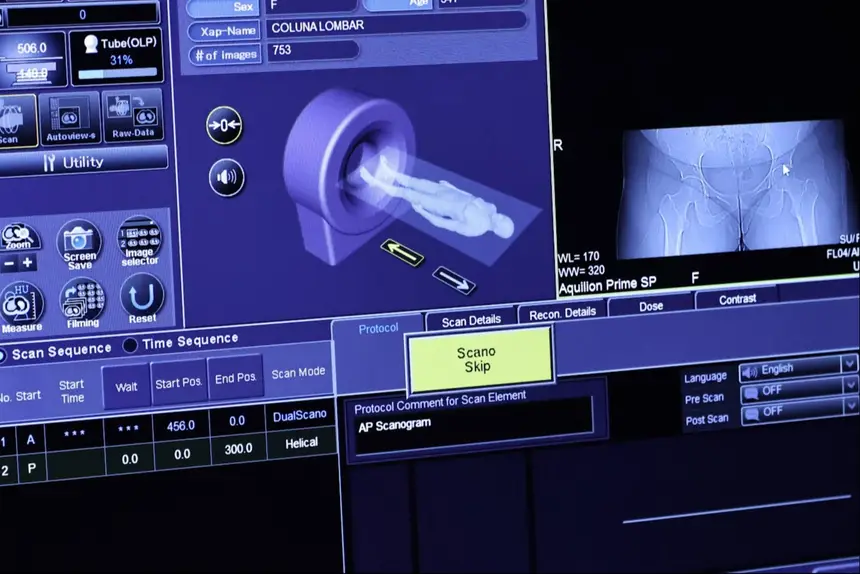

O Centro Tecnológico é composto por aparelhos de ressonância magnética, tomógrafo computadorizado, equipamento de mamografia, raio X telecomandado e densitometria óssea.

Os equipamentos foram adquiridos por meio de contratação e fazem parte do plano de qualificação de exames por imagem.